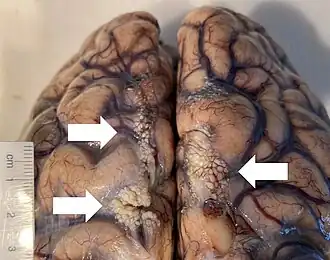

Arachnoid granulations seen on autopsy, where the dura mater has been removed but the arachnoid mater is left in place. | |